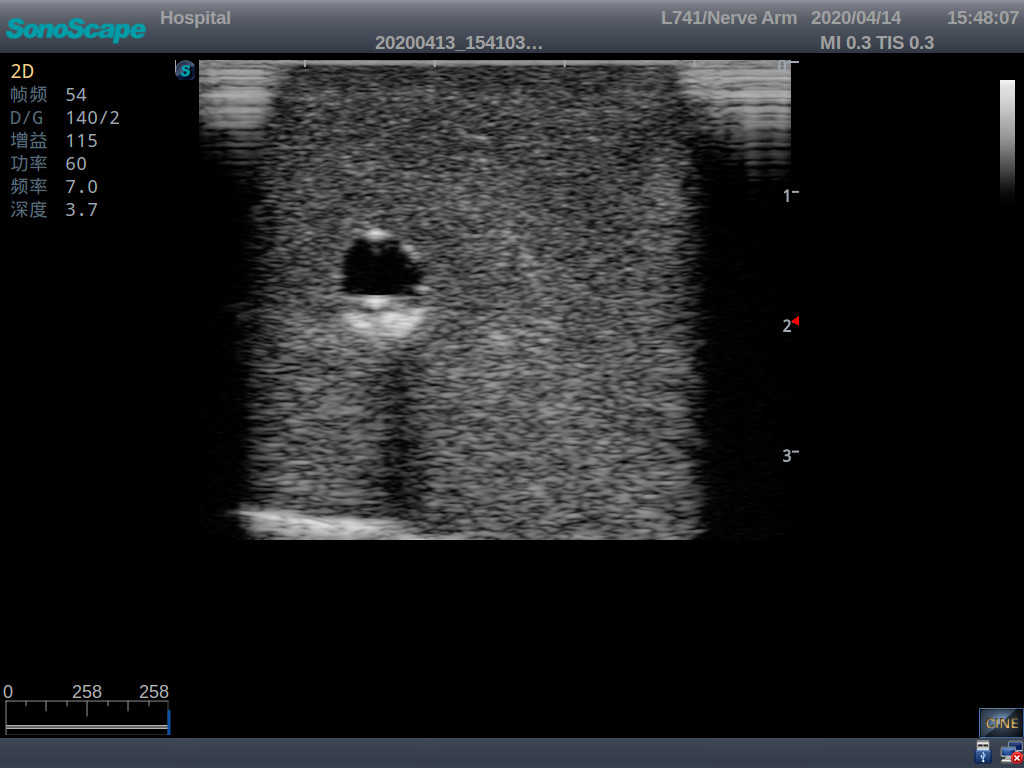

Product size(mm) 700×500×160

It is a model covering up from lobulus auriculae plane to the umbilical plane, and it has anatomical structures like clavicle, rib, sternocleidomastoid, jugular vein and basilic vein.

1)   Made of high molecular polymer ultrasound material, close to the real skin

2)   It can be used by real ultrasound machines

3)   Clear and real images of the tissues and organs (basilic vein and superior vena cava)